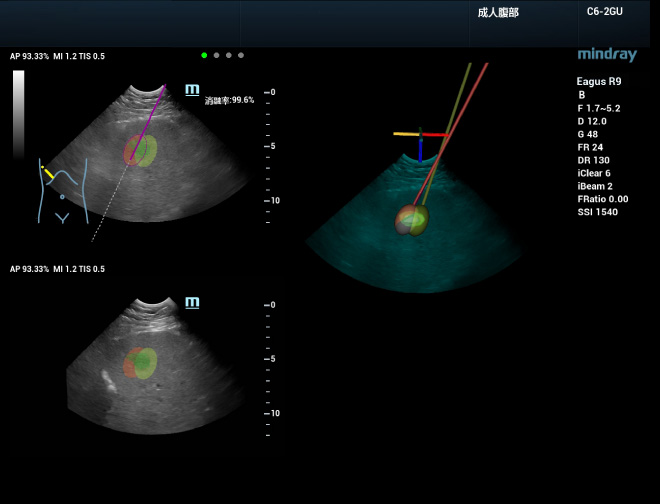

Met meer vertrouwen een behandeling uitvoeren

Tijdens de planning van 3D-ablatie kan ablatiesimulatie worden uitgevoerd om een effectieve behandelstrategie te ontwikkelen voor grote laesies die met meerdere naalden moeten worden verwijderd. Stel eerst het ablatiebereik voor individuele naalden in en plaats vervolgens de naalden voor ablatie in de simulatie. Er kan optimaal plan worden gemaakt door de realtime weergave van de dekkingsgraad van de laesie te observeren. Dit proces ondersteunt driedimensionale weergave vanuit meerdere hoeken, waardoor intu?tieve en multidimensionale observatie van de ablatiedekking voor de gehele tumor mogelijk is. De naald kan dan volgens het geplande pad in de echte tumor worden geleid, en de ablatiedekking wordt in real time bijgewerkt met de daadwerkelijke inbrenging van de naald. Met uHit Fusion kan het hele ablatieproces beter worden gepland en gestandaardiseerd, zodat de gebruiker minder afhankelijk is van ervaring.

Nauwkeuriger een klinische diagnose stellen

Een uitgebreide en onmiddellijke evaluatie na de ablatie is van vitaal belang voor het opsporen van resterende tumoren en het onmiddellijk uitvoeren van een aanvullende behandeling, waardoor de kans op volledige ablatie wordt vergroot en het optreden van lokale progressie wordt voorkomen. Het team van Prof. Xie kan onmiddellijk na de procedure 3D-echografie van de ablatieplaats uitvoeren en deze vervolgens samenvoegen met de 3D-echografiegegevens om een volledig beeld te krijgen van de vraag of de ablatieplaats de veilige grens van de laesie in de gehele 3D-ruimte bestrijkt en of er sprake is van een restlaesie of onvoldoende ablatie. Bovendien kunnen tomografische segmentatieweergave en 3D-volumereconstructie van dit fusiebeeld worden uitgevoerd om de ruimtelijke locatie van het gebied dat aanvullende behandeling nodig heeft en de relatie met de omliggende vitale organen duidelijker te visualiseren.